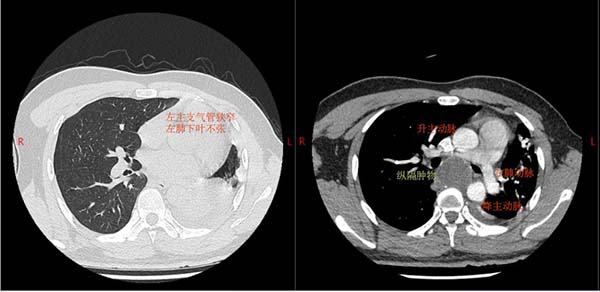

30 岁患者小陈因胸痛查出后纵隔 5×4 厘米肿物,辗转多家医院均束手无策。这个 “定时炸弹” 长在气管隆突下方、食管前方,不仅压迫左主支气管完全闭塞、左肺无法张开,同时肿物被左肺动脉主干和主动脉紧紧 “包裹”,常规左侧胸腔入路根本无法触及肿物,甚至术中左侧单肺通气都做不到——这意味着术中的氧合维持成了最先面对的巨大挑战。